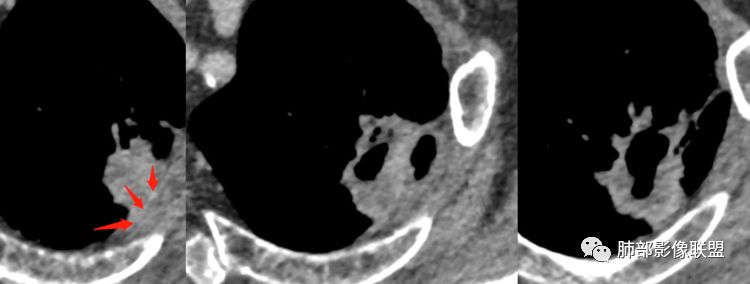

Lotus:支持恶性的征象,假大空,支持良性的征象环形强化RockJ-ason:老年男性,吸烟史,不规则厚壁,周围有囊腔,中等度强化,无卫星灶,首先考虑恶性,有些支持鳞有些支持腺,拿不准RockJ-ason:鉴别结核一切∮随缘:左肺上叶空洞,洞壁较厚,不规则,紧贴胸膜,有血管牵拉,增强后轻度强化,周围有肺气肿,老年男性,考虑鳞癌,鉴别结核(周围比较单一,无树丫)

杨泽锋:空洞壁上有空气,这一点支持炎性病变,可惜病史又不支持慢性肺脓肿

南边:囊腔,壁局限性不规则增厚

尘缘:空腔壁厚薄不均,内壁有结节样改变,强化不均匀明显强化,有坏死。doctor:病灶囊中囊,壁中囊,考虑腺癌?

心灵鸡汤:左肺尖团状影,内有空洞,似有壁结节,边缘有毛刺,周围见局限性肺气肿,考虑恶性肿瘤,腺癌?鉴别空洞型肺结核,肺脓肿南边:胸膜也不踏实

尘缘:胸膜是有栽桩改变